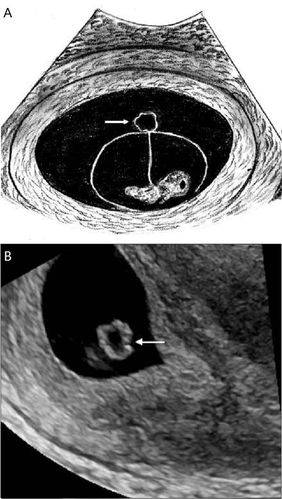

图 8 声像图示左侧残角子宫宫腔内可见妊娠囊,其内可见卵黄囊及胎芽